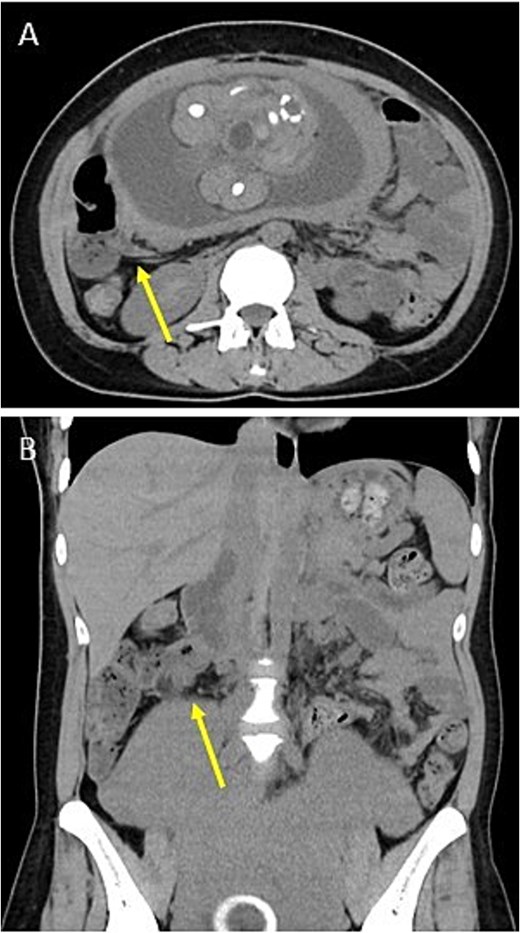

A 34-year-old woman (gravida 3, para 1) presented at 28 weeks of gestation with a chief complaint of right abdominal pain that began in the morning. She had no history of gynecological problems. Blood tests showed an increased white blood cell (WBC) count of 17 080/μl and C-reactive protein (CRP) concentration of 3.01 mg/dl. Abdominal ultrasonography revealed a small amount of ascites on the right side of the abdomen; however, the appendix could not be detected. Similarly, an abdominal computed tomography (CT) scan did not reveal the appendix (Fig. 1), and gynecological diseases were ruled out. However, as her abdominal pain worsened in the evening, we diagnosed her with acute appendicitis and decided to perform surgery that night.

Preoperative images. Plain CT shows no appendix in the axial plane (A) or the coronal plane (B). Arrows indicate the terminal ileum.